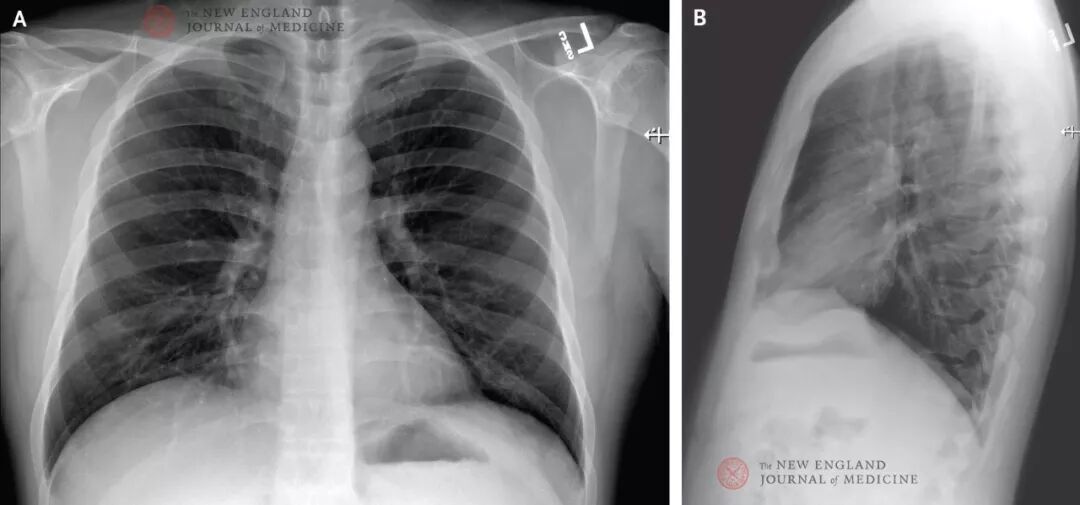

First Case of 2019 Novel Coronavirus in the United States

除有高血脂病史外,该患者不吸烟者且平素健康。体格检查:体温为37.2°C,血压为134/87 mm Hg,脉搏为110/分,呼吸为16次/分,患者呼吸环境空气时的氧饱和度为96%。由于肺部听诊出现干啰音,故进行胸片检查,结果为未见异常(见图1)。快速核酸扩增检测(NAAT)显示甲型和乙型流感抗原呈阴性。取鼻咽拭子用NAAT进行呼吸道病毒的病原体检测;48小时后报告所有检测病原体结果为阴性,包括甲型和乙型流感病毒、副流感病毒、呼吸道合胞病毒、鼻病毒、腺病毒和4个可以致人类发病的冠状病毒(HKU1、NL63、229E、OC43)。基于患者旅行史,医生立即上报地方和国家相关卫生管理部门。汇同急诊医师,华盛顿卫生健康部立即报告了美国CDC应急管理中心。尽管患者表示没有去过武汉海鲜市场且在华旅行期间也没有接触过任何病患,但CDC工作人员依据目前的CDC“需调查人员”病例定义,一致同意对该患者进行2019-nCov检测[8]。我们按CDC指南对患者进行了样本采集,包括血清、鼻咽拭子、口咽拭子样本。样本采集后,对患者进行了在当地卫机构的监控下的居家隔离。2020年1月20日,CDC证实通过采用实时逆转录酶聚合酶链检测方法(rRT-PCR),该患者鼻咽拭子和口咽拭子2019 新型冠状病毒(2019-nCov)检测结果为阳性。通过与美国CDC相关专家,国家和当地的健康官员,急诊医疗中心,医院管理层和员工的通力合作,该患者被收治进入普罗维登斯医疗中心的隔离病房进行医学观察,医务人员按照CDC建议进行了相应防护(包括眼部防护),以防止接触,飞沫,气溶胶等污染[9]。收治入院后,患者出现了持续性干咳,恶心和呕吐2天;患者自诉无呼吸困难和胸痛,且生命体征都在正常范围内。体格检查发现患者出现粘膜干燥,其他检查没有明显异常。住院后,对患者进行了支持治疗,包括2L的生理盐水静滴和昂丹司琼缓解恶心症状。图2. 按照患者发病及住院日期(2020年1月16日至2020年1月30日)列出的症状和最高体温。